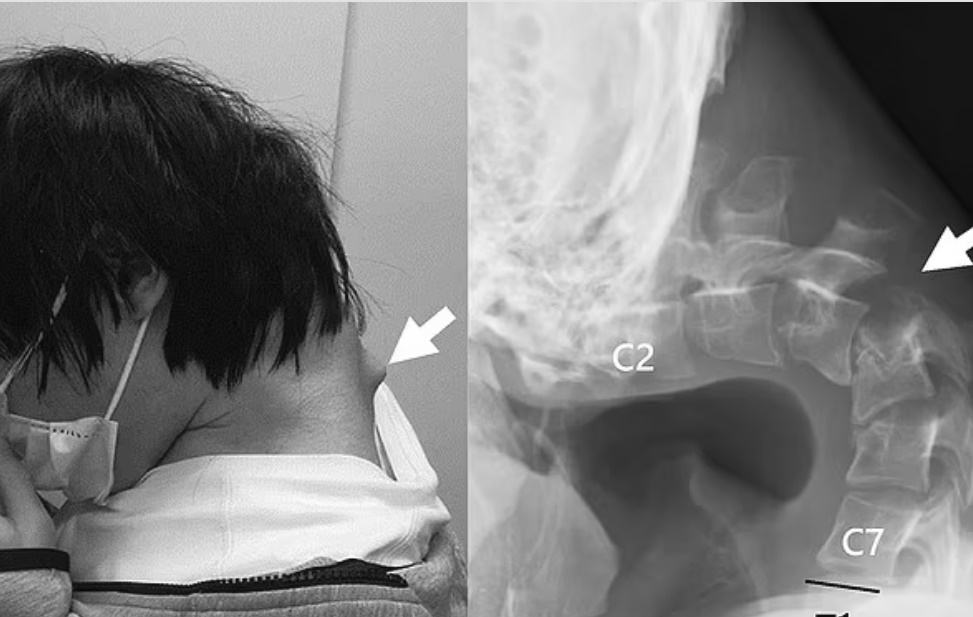

| 스마트폰으로 하루에 몇 시간씩 게임을 하던 20대 남성이 ‘머리떨굼 증후군’ 진단을 받았다. 목뼈가 휘어지면서 목 뒤에 혹이 생긴 모습 [데일리메일] |

14일(현지시간) 데일리메일은 장시간 고개를 숙인 채 스마트폰을 보던 습관 탓에 목이 꺾여 머리를 들어올릴 수 없게 된 일본 25세 남성의 사례를 보도했다.

이 남성은 10대 초반에 괴롭힘을 당한 뒤 학교를 그만 두고 집에 틀어박혀 지냈다고 한다. 그의 유일한 취미는 스마트폰 게임이었고, 매일 몇 시간씩 고개를 숙인 채 휴대폰을 보는 것이 일상이었다.

하지만 이러한 생활 습관이 반복되면서 목과 척추뼈가 기이하게 꺾여 척추가 탈구되는 증상까지 나타났다. 탈구는 척추뼈 사이에 있는 인대나 추간판이 늘어나거나 찢어져 척추뼈가 열에서 벗어나는 것을 말한다. 또한 남성은 목뼈가 휘어지면서 목 뒤에도 혹이 생겼다.